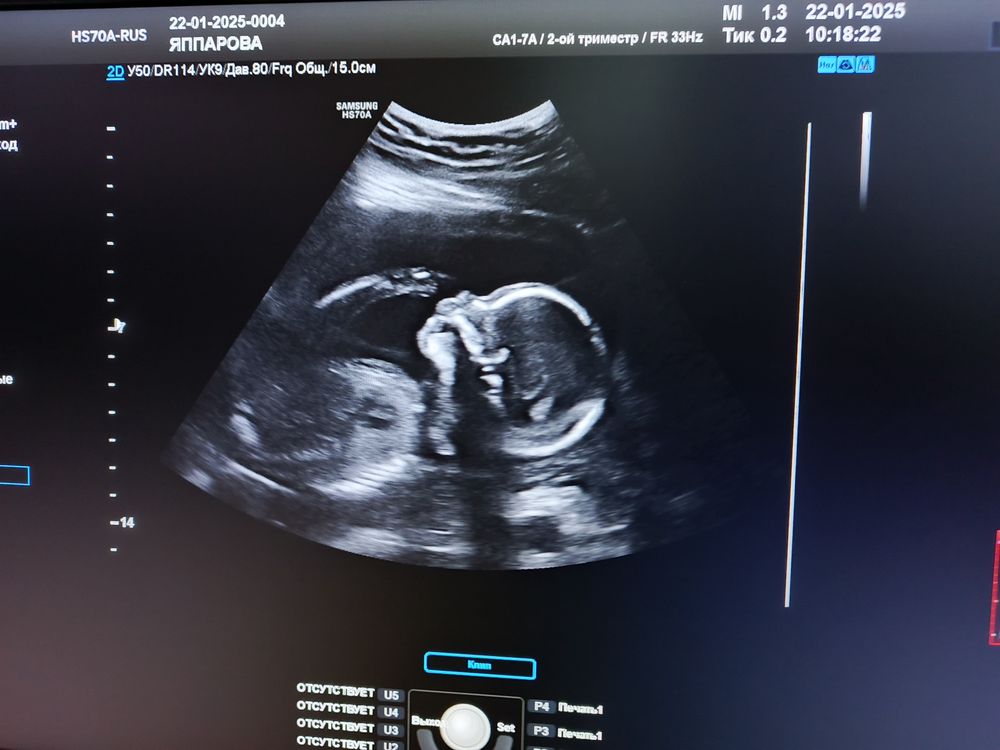

Марина в Клуб беременных 10 месяцев Пол ??? Пол малыша Здравствуйте. Виден пол ? 🤣 фото в комментах Посмотрите еще 20 записей на эту тему Лучший ответ Юленька Это какое место сфоткано 🤣 Вам врач на таком сроке не сказал? 02.02.2025 Ответить Юленька Юленька, по второму фото хоть понятно что где) но там голова и животик, половые органы ниже, не в кадре( 02.02.2025 Ответить Марина Юленька, прикрепила ниже , может что видно 🤣 02.02.2025 Ответить Марина Комментарий удален 02.02.2025 Ответить Марина Юленька, сказала , но я сомневаюсь так как нечего на снимках не вижу 🤣сказали будет мальчик 02.02.2025 Ответить Отменить Ответить Марина 02.02.2025 Ответить Мария Нужно фото вбок где будет видно половой бугорок, по профилю лица пол не определить 02.02.2025 Ответить Марина Мария, прикрепила ниже 02.02.2025 Ответить Мария Марина, мальчик 02.02.2025 Ответить Кира Виден только ребенок 02.02.2025 Ответить Марина Кира, прикрепила ниже 02.02.2025 Ответить Victoria Фото нет 02.02.2025 Ответить Марина Victoria, 02.02.2025 Ответить Марина Victoria, 02.02.2025 Ответить Victoria Марина, тут точно не видно. 02.02.2025 Ответить Марина Victoria, блин фотки не могу прикрепить , у всех такие проблемы , типа не загружает 02.02.2025 Ответить Марина Victoria, а ниже 02.02.2025 Ответить Gulnar Mamedova Марина, на мальчика похож 03.02.2025 Ответить Пол по крови. Вероятность ошибки😏 У нас будет ЗДОРОВЫЙ сынок🙏🏼🙏🏼🙏🏼🙏🏼 Чаты Беременных Выберите чат: Январята-2026 Февралята-2026 Мартята-2026 Апрелята-2026 Майчата-2026 Июнята-2026 Июлята-2026 Августята-2026